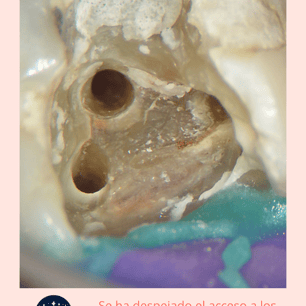

Calcificaciones: Se utilizan instrumentos especiales, como limas ultrasonicas, para localizar y remover las calcificaciones.

Limpieza y Desinfección: El conducto radicular se limpia y desinfecta una vez que las calcificaciones se han eliminado.

Resultados esperados: Recuperación del diente y eliminación del bloqueo en los conductos radiculares.